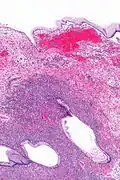

Mucinous cystadenoma

| Micrograph showing a mucinous cystadenoma of the ovary. H&E stain. | |

Mucinous cystadenoma is a benign cystic tumor lined by a mucinous epithelium. It is a type of cystic adenoma (cystadenoma).